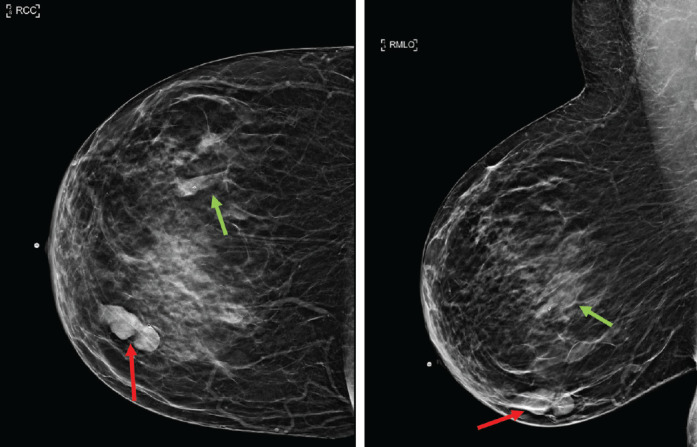

Rosai-Dorfman disease (RDD) is a self-limited, idiopathic, non-neoplastic disorder characterized by the proliferation of phagocytic histiocytes, which can mimic malignant lymphoproliferative disease. Cases of RDD most commonly present as bilateral painless cervical lymphadenopathy, with lesser involvement of the axilla, inguinal, and mediastinal lymph nodes. We present the case of a 62-year-old woman with a history of endometrial serous carcinoma who underwent evaluation at a dedicated breast imaging department after positron emission tomography/computed tomography (PET/CT) revealed breast masses and axillary nodes with increased uptake of fluorodeoxyglucose (FDG). Upon clinical examination, she had bilateral palpable lumps in both breasts and axillae. Subsequent dedicated breast imaging with bilateral diagnostic mammography with tomosynthesis and bilateral complete breast ultrasound were suspicious for malignancy detecting bilateral breast masses and axillary lymphadenopathy corresponding to the FDG-avid findings on PET/CT. Ultrasound-guided core needle biopsies, however, revealed a diagnosis of RDD. This case highlights the unique characteristics of RDD with an atypical clinical presentation suspicious for breast cancer both clinically and radiologically.